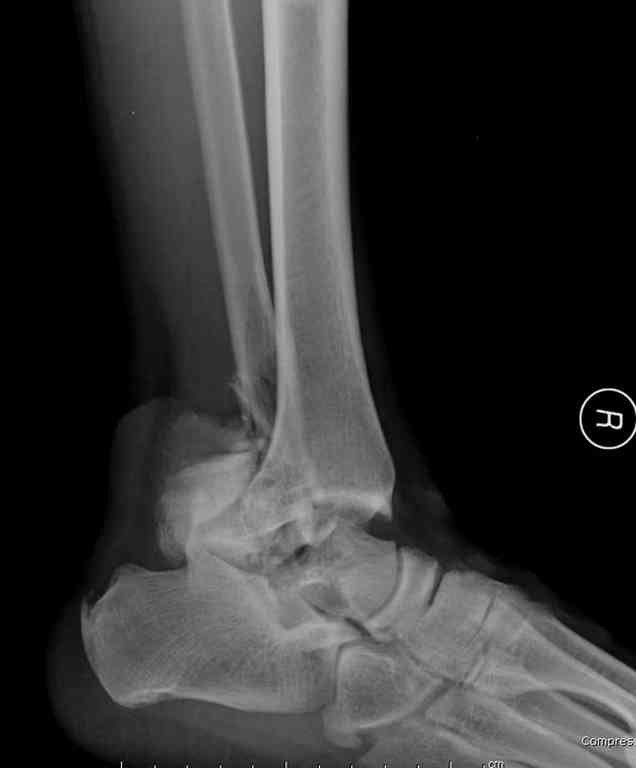

Второй случай прооперирован вчера.

10 дней назад поступил с открытым повреждением медиальной лодыжки и переломо вывихом таранной кости. Ургентно сделана репозиция с наложением наружного фиксатора + Irrigation&Debridment.

Во время репозиции выявили повреждение заднего сухожилия м. тибиалис и задней большеберцовой артерии. Медиальную рану удалось закрыть частично и установлен вакуум.

Дважды провели Irrigation&Debridment с заменой вакуума.

Вчера провели фиксацию.

Из-за многооскольчатости дистальной части малоберцовой, где невозможно было провести фиксацию шурупами, перелом зафиксирован подпирающей пластиной, которая должна служить дополнением отсутствующей дистальной части малоберцовой (lateral cortex substitute).

Для стабильности два шурупа на синдесмоз.

Медиальную рану с приближенными краями продолжаем вакуумировать (KCI). Наружный фиксатор оставлен на пару недель, надеюсь, небольшая рана будет гранулировать и закроется без кожной пластики. Фиксация медиальной ложыжки не планируется.